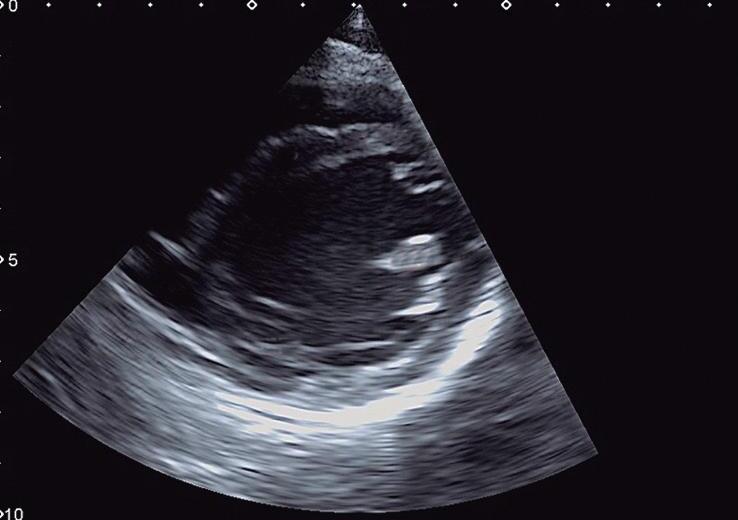

O plano paraesternal pode ser obtido com o paciente em decúbito dorsal ou em decúbito lateral esquerdo. Inicialmente, em geral, obtemos o plano paraesternal eixo longo do VE com o transdutor posicionado na borda esternal esquerda média do paciente e com o index direcionado para o seu ombro direito (Fig. 1-5a e ▶ Vídeo 1-13). Nesse plano, é possível avaliar as vias de saída e entrada do VE e sua contratilidade e mensurar as dimensões das cavidades esquerdas e da aorta (raiz, junção sinotubular e porção ascendente) (Fig. 1-6a; ▶ Vídeos 1-14 e 1-15). Os óstios das artérias coronárias e a continuidade mitroaórtica também podem ser avaliadas. Com discreta movimentação anterior do transdutor, podemos obter o eixo longo do VD e analisar suas vias de entrada e saída (valvas tricúspide e pulmonar) (Fig. 1-6b, c; ▶ Vídeos 1-13 e 1-16).

Fig. 1-6. Plano paraesternal eixo longo (2D e Doppler): eixo longo do VE diástole (a) e sístole (b); eixo longo do VD com sua via de entrada (c) e eixo longo do VD com sua via de saída (d). AD: átrio direito; AE: átrio esquerdo; VD: ventrículo direito; VE: ventrículo esquerdo; Ao: aorta; M: valva mitral; AP: artéria pulmonar; VT: valva tricúspide; VP: valva pulmonar; AP: artéria pulmonar; SIV: septo interventricular.